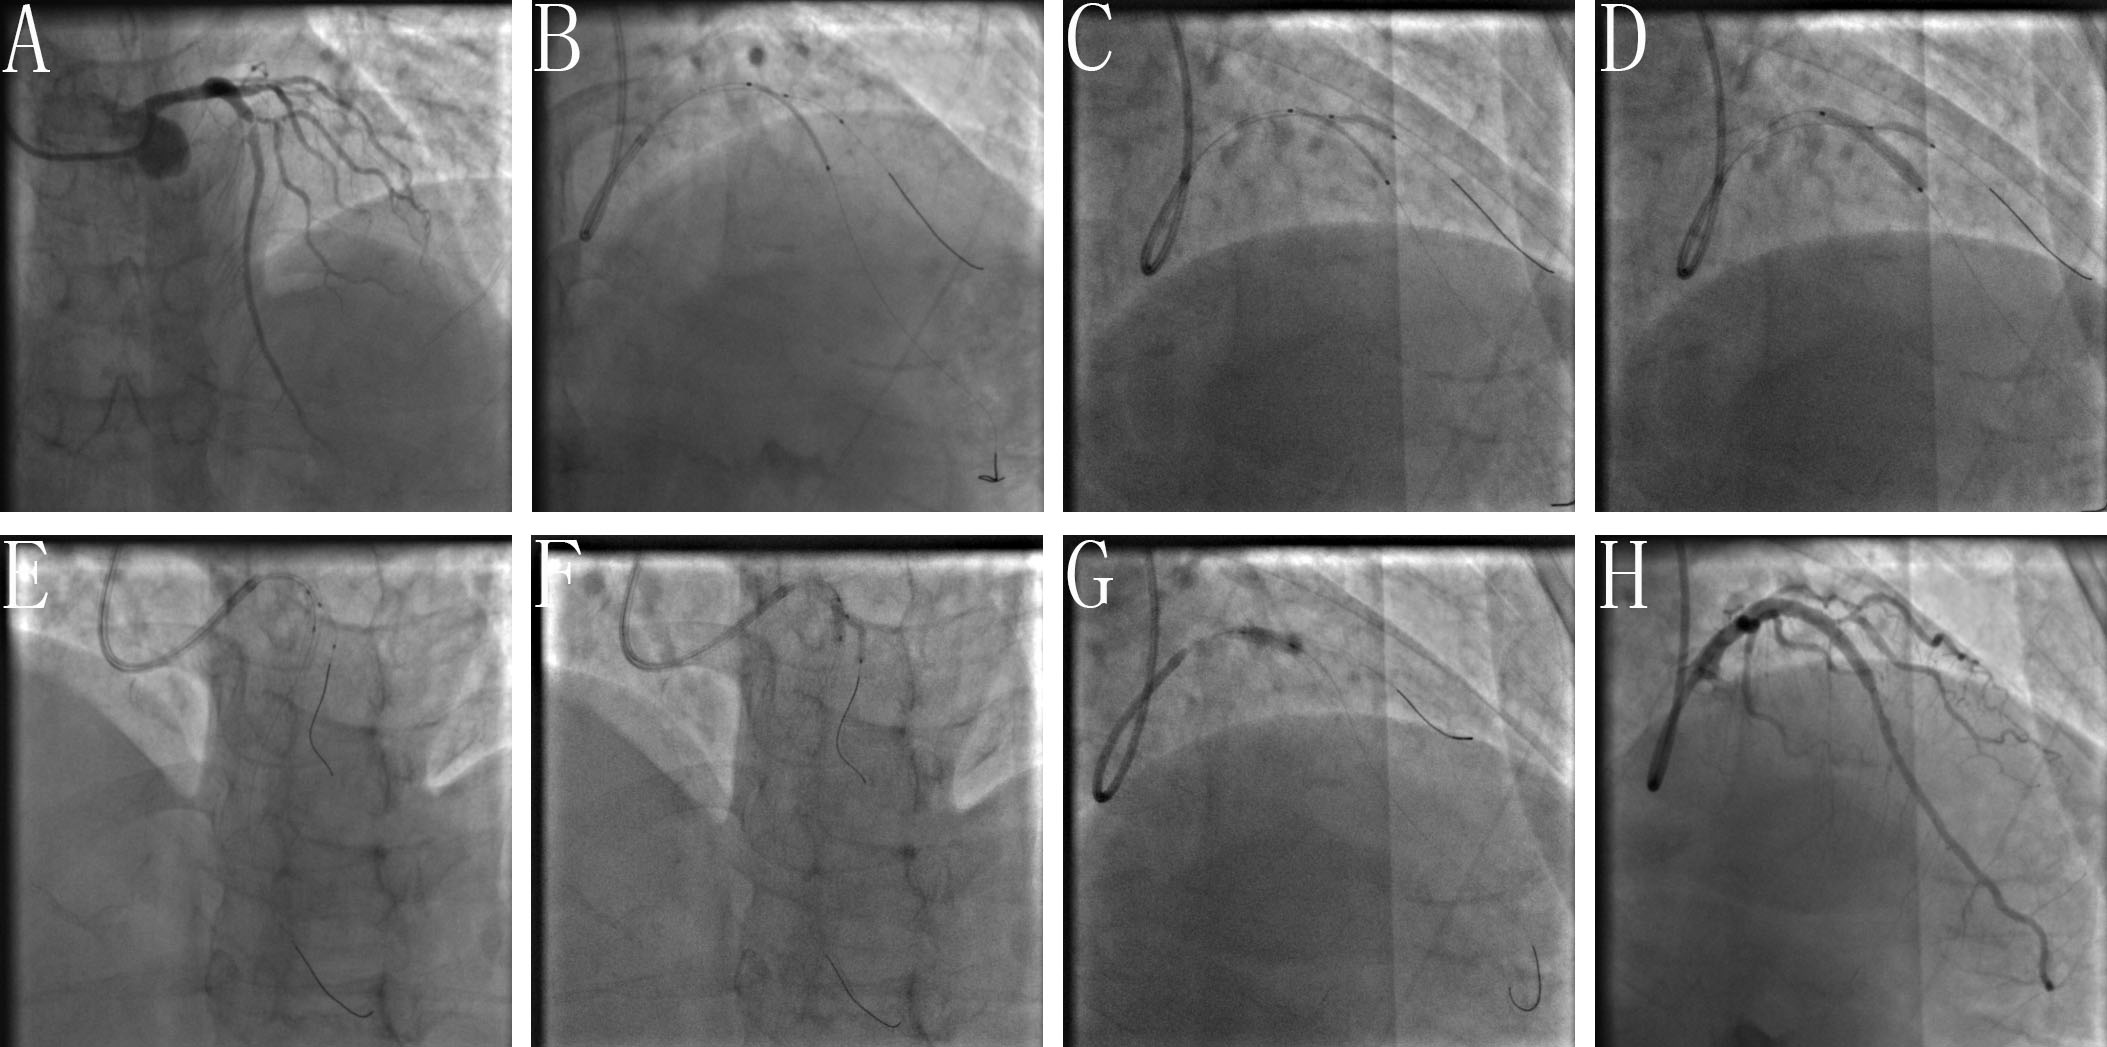

BOOT: the procedural steps of BOOT include: (A) wiring the SB and MV and pretreating either branch as indicated; (B) performing sequentially snuggling balloon-stent dilation (SBSD) by the following steps: pre-staying a compliance balloon in the SB with its proximal maker in the bifurcation core and then properly positioning of the MV stent; first inflating the SB balloon and then the stent balloon, followed by first deflating the stent balloon and then SB balloon; (C) conducting the proximal optimization technique (POT) at the operator’s discretion; (D) rewiring the SB closest to the carina; (E) performing sequentially kissing or snuggling balloon dilation (SKBD/SSBD) with preference to the latter: placing 2 non-compliance balloons with mini-juxtaposition or snuggling-position in the bifurcation core and sequentially inflating the SB and MB balloons with simultaneous deflation; (F) finalizing the procedure with (re)-POT (Fig. 1).

Fig. 1.The procedural steps of BOOT. (A) Wiring the SB and MV and pretreating either branch as indicated. (B) Performing sequentially snuggling balloon-stent dilation (SBSD) by following steps: pre-staying a compliance balloon in the SB with its proximal maker in the bifurcation core and then properly positioning of the MV stent; first inflating the SB balloon and then stent balloon, followed by first deflating the stent balloon and then SB balloon. (C) Conducting proximal optimization technique (POT) at operator’s discretion. (D) Rewiring the SB closest to the carina. (E–G) Performing sequentially kissing or snuggling balloon dilation (SKBD/SSBD) with preferred the latter: placing 2 non-compliance balloons with mini-juxtaposition or snuggling-position in the bifurcation core and sequentially inflating the SB and MB balloons with simultaneous deflation. (H) Finalizing the procedure with (re)-POT.